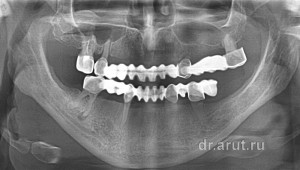

На приём в стоматологическую клинику пришла пациентка Н., которая была протезирована 20 лет назад в Москве. Суть её ортопедического лечения заключалась в изготовлении штампованно-паяного мостовидного протеза с опорами 16-15-23-27 зубы на верхней челюсти и с опорами на 46-43-33-35 зубы нижней челюсти. Протезы прослужили 20 лет. На ортопантомограмме изображены мостовидные протезы после 20-летнего срока службы.

По всем законам природы, в частности билатерального строения человека, данные мостовидные протезы должны были расшатать или сломать опорные зубы через несколько месяцев службы, но как ни странно прослужили («простояли») 20 лет! Но если обратить внимание верхний левый клык разрушился под коронкой и в течение 20 лет, выдвигаясь и разрушаясь, практически полностью разрушился, сохранив микроскопический корень. На момент осмотра пациентки, опорами мостовидного протеза являлись только 2 зуба — 15 и 27! Таким образом мостовидный протез с протяжённостью в 12 зубов удерживался только на 2 зубах! В итоге это привело к расшатыванию 15-го зуба.